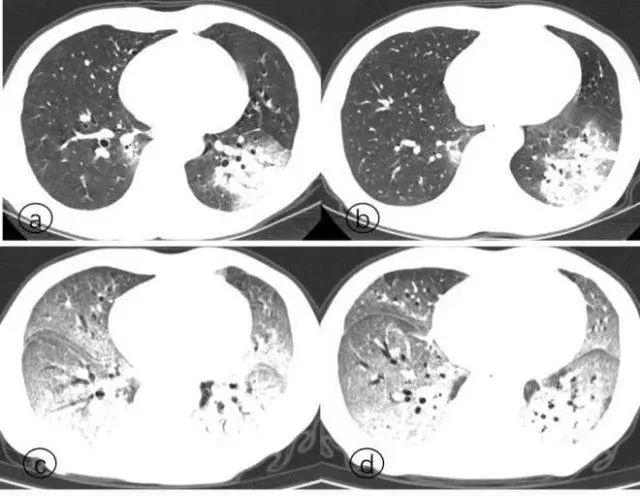

而解剖发现,新冠死者的肺遭到病毒攻击,肺泡损伤,有大量粘稠的分泌物从肺泡里溢出来,CT上看肺变成了一大片白色,医学上叫“白肺”。

患者逐渐演变为白肺的过程

打个不严谨的比方,白肺就像你洗手的时候,把肥皂放在海绵上,过不了几天,你捏一捏海绵,那个白腻腻、黏唧唧的样子,它没法再吸水(吸氧换气)了。

轻症患者用呼吸机能维持,是因为他们的肺还能部分工作;

而重症患者的“白肺”已经报废了,你再怎么给他上呼吸机也白搭,最后就会因呼吸衰竭而死。